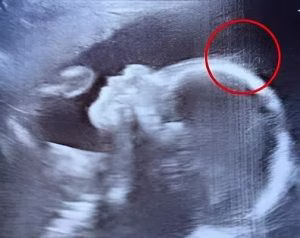

Doctors couldn’t believe what they saw during the ultrasound. But when the baby girl was born, her charm, strength, and story touched hearts around the world in the most unexpected way.

When 29-year-old Emily Foster from Kent, England, walked into the hospital for her 20-week pregnancy scan, she expected the usual routine: a grainy image, a few measurements,…